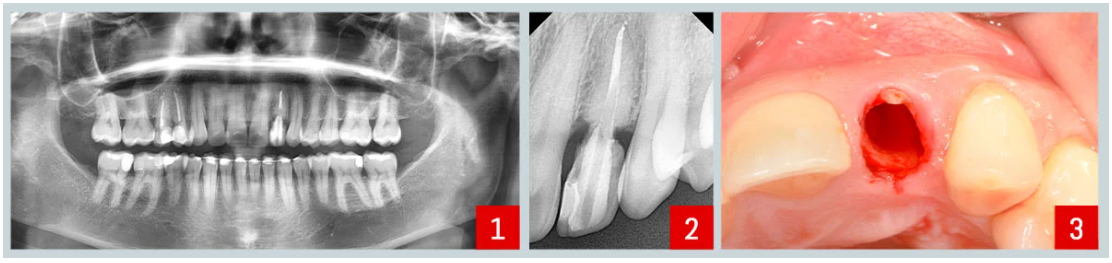

Situación inicial : (imágenes 1 y 2)

El paciente presentaba movilidad en el incisivo lateral superior izquierdo. La evaluación clínica no reveló movilidad radicular ni signos de infección, y solo una leve pérdida ósea en la papila mesial. Optamos por un abordaje mínimamente invasivo para preservar el nivel óseo existente y prevenir la reabsorción futura en áreas críticas como la placa bucal y la papila. El procedimiento elegido fue la técnica de protección del alvéolo.